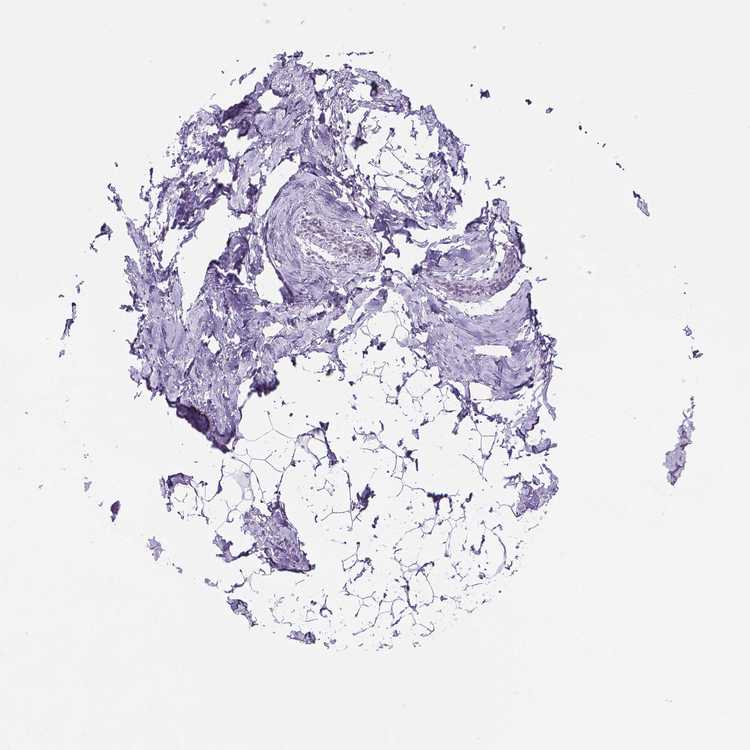

TISSUE PRIMARY DATA BREAST Show tissue menu

BREAST - Antibody stainingi

Antibody staining in the annotated cell types in the current human tissue is reported as not detected, low, medium, or high, based on conventional immunohistochemistry profiling in selected tissues. This score is based on the combination of the staining intensity and fraction of stained cells.

Each image is clickable and will lead to virtual microscopy that enables deeper exploration of all samples and also displays staining intensity scores, fraction scores and subcellular localization as well as patient and tissue information for each sample.

Antibody HPA024216

Adipocytes Not detected

Glandular cells Not detected

Myoepithelial cells Not detected